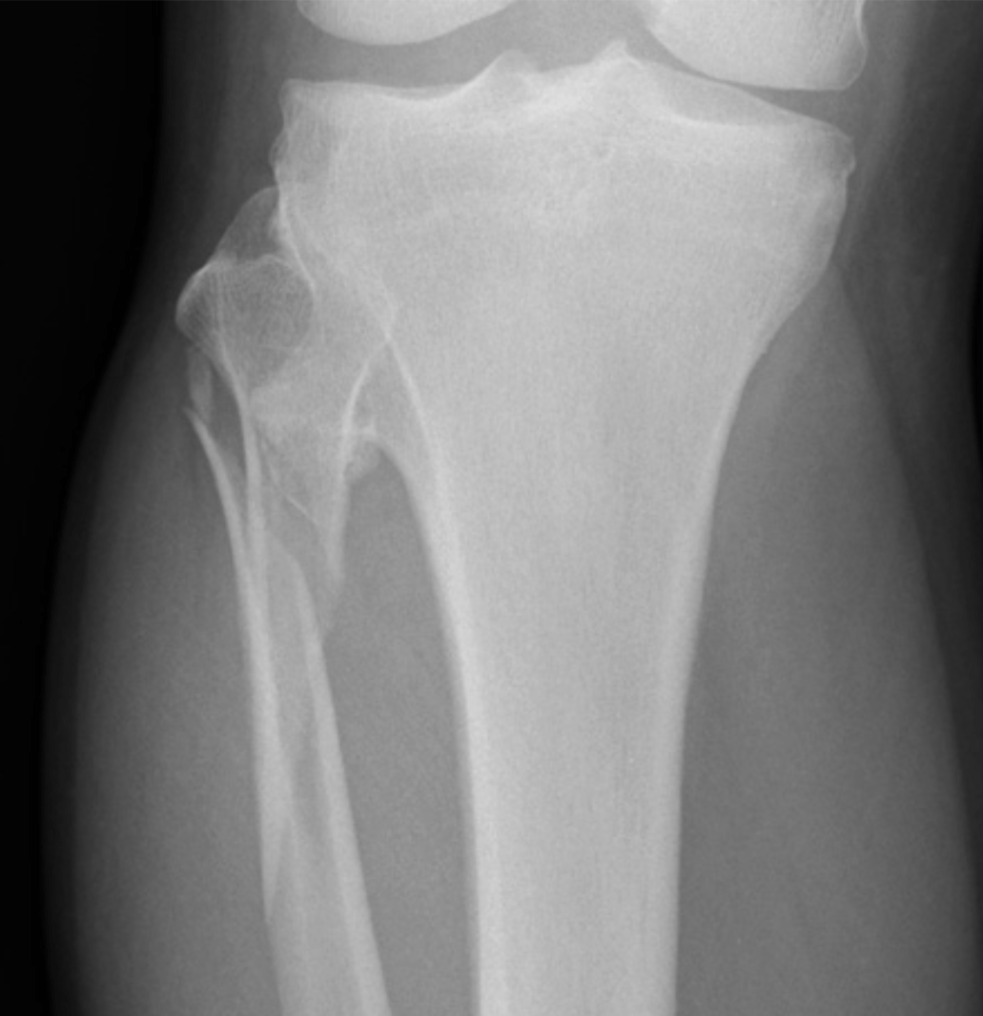

What should you suspect if you see this image?

What is Maisonneuve Fracture?

Fracture of the proximal fibula associated with injury to the medial side of the ankle and disruption of the distal tibiofibular syndesmosis.

The medial ankle injury may be either a visible medial malleolus fracture or an invisible injury of the medial ligaments.